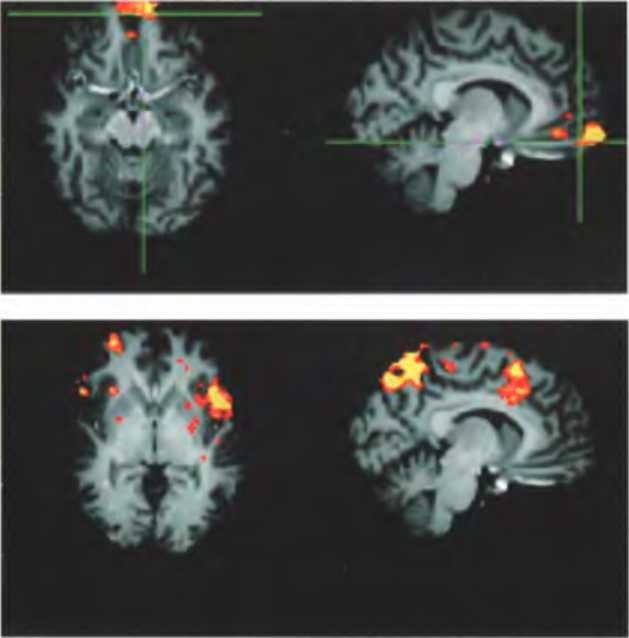

Человеческий мозг обращается с утверждениями, которые считает истинными, совсем не так, как с утверждениями, которые он считает ложными. Утверждения первого типа обычно влияют на направление дальнейших мыслей и действий, в то время как утверждения второго типа не принимаются во внимание. В ходе одного исследования была выявлена функциональная разница между “верящим” и “не верящим” мозгом. Участников эксперимента знакомили с множеством разнообразных утверждений и просили высказывать суждения, правда это или неправда.

В мозге человека, который верит тому, что ему говорят (вверху) активны области, ответственные за объединение эмоций и мыслей, а в мозге человека, который не верит (внизу), активируются края островка, расположенного на глубокой складке между лобной и височной долями Островок чувствителен к вещам, вызывающим у нас отвращение. Это заставляет предположить, что восприятие лжи мозгом во многом подобно восприятию нездоровых субстанций, которые наш организм отвергает11.

Судя по результатам сканирования нашего головного мозга, хотя в принятии решений о том, истинно или ложно утверждение, задействованы многие из высших когнитивных отделов головного мозга, окончательный выбор, похоже, остается за более примитивными отделами, связанными с эмоциями. К их числу относится передняя поясная кора — область, ответственная (в числе прочего) за объединение эмоциональных реакций с нашими мыслями и суждениями, а также кора островка — область, чувствительная к “отвратительности”. Участие в этих процессах островка заставляет предположить, что ложь может вызывать у нас подлинное отвращение.